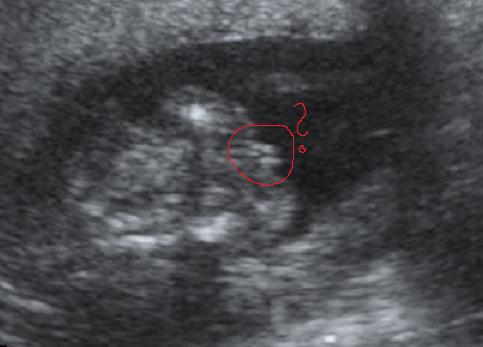

Anno a fiammal a 33.héten uh-on azt mondták, hogy kislány, vagy egy szemérmes fiú... örültem, mint majom a farkának....de jó... kislányom lesz! És mi lett? Egy gyönyörű kisfiam!